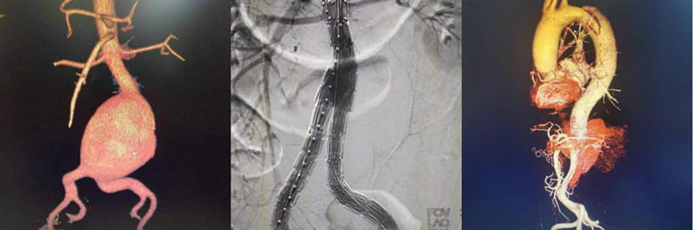

血管疾病專(zhuan) 業(ye) 組:常規開展主動脈夾層的腔內(nei) 手術、胸主動脈瘤、腹主動脈瘤的腔內(nei) 手術和開放手術、頸動脈內(nei) 膜剝脫和支架置入手術、肝硬化、門靜脈高壓症斷流、脾腎靜脈及門腔靜脈分流、下肢動脈閉塞症、深靜脈血栓形成、糖尿病足、血栓閉塞性脈管炎、動脈栓塞等疾病的外科血管旁路搭橋,血管成型,靜脈動脈化,球囊導管取栓,腔靜脈濾器植入,腸係膜靜脈血栓形成經股動脈穿刺腸係膜上動脈持續溶栓治療,大、小隱靜脈曲張微創手術,下腔靜脈、股動脈等血管損傷(shang) 的救治。並成功開展目前最前沿的高難度主動脈弓三開窗腹膜分支支架置入術。

腹主動脈腔內(nei) 隔絕術